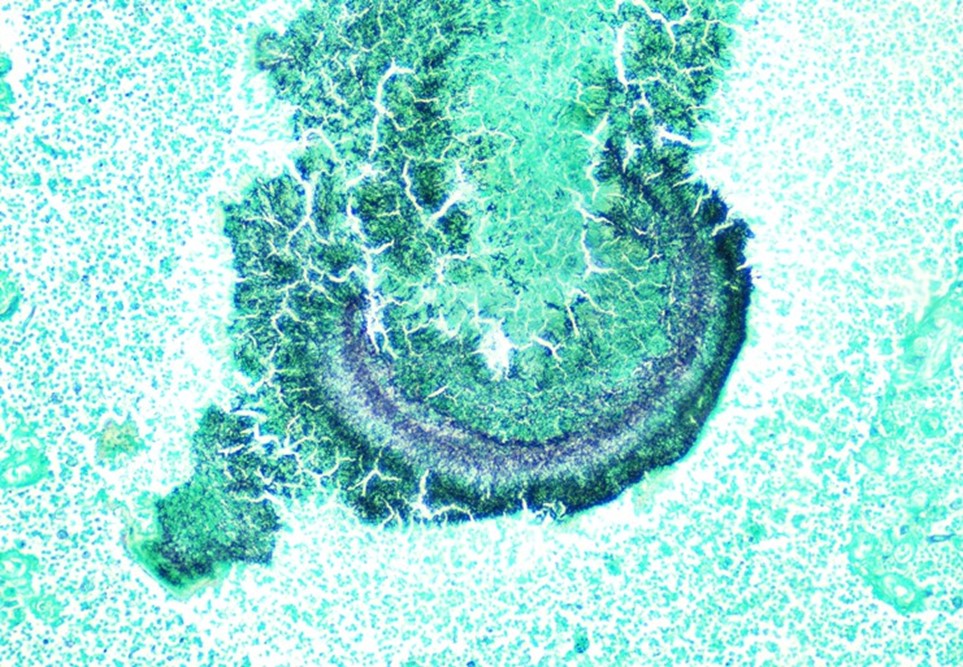

On admission, a CT scan of the abdomen and pelvis revealed a 3.5 x 1.9 cm air and fluid collection of the inferior border of the spleen and 5.2 x 1.6 cm fluid collection of lateral spleen. The collections were noted to be increased compared to the prior imaging 6 weeks before. Blood cultures were without growth at 5 days. A transthoracic echocardiogram showed no significant valvular abnormalities or vegetations. On hospital day 5, the patient was taken to the operating room for a laparoscopic splenectomy and left diaphragm repair. Surgical findings included a large spleen with omental adhesions and a thick rind along the spleen, which was closely adherent to the diaphragm. A portion of the colon closely adherent to the spleen was also noted. Histopathologic examination showed multifocal splenic abscesses with surrounding fibrosis on hematoxylin and eosin (H&E) stain and granules with surrounding Splendore-Hoeppli material on higher magnification (Figure 1). On Grocott-Gomori methenamine silver (GMS) stain, the granule was seen to be composed of mixed bacterial morphologies with a predominance of filamentous rods typical of Actinomyces (Figure 2). Based on histopathological examination, a diagnosis of splenic actinomycosis was rendered.

Although most actinomycotic lesions are polymicrobial, species of the genus Actinomyces are the predominant etiologic agents.2 Actinomyces are a group of gram positive filamentous facultatively anaerobic or microaerophilic bacteria that are normal flora of the gastrointestinal and genitourinary tracts. The organisms typically have true branching and may appear beaded due to irregular Gram staining. Importantly, Actinomyces spp. will be negative with modified acid-fast staining, which can be used to differentiate it from Nocardia spp. The bacteria are relatively slow growing on primary culture and mature colonies may have a variety of morphologies. The classic “molar tooth” appearance is characteristic of A. israelii.3 On histopathology, actinomycotic lesions have a surrounding area of fibrosis and central suppurative inflammation with granules. The granules consist of accumulations of organisms with club-shaped ends and filamentous rods seen on special staining.4 Optimal diagnosis would consist of visualization of these features on histopathology or other direct method. Isolation of the organism can be useful but should be taken in the context of the clinical picture as the mere isolation of Actinomyces in culture does not always imply actinomycosis.